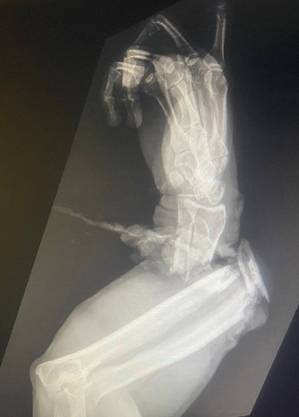

Greg Graziani, de 53 anos, diretor de vida selvagem do zoológico, foi mordido por um grande jacaré que praticamente decepou a parte inferior do braço esquerdo, como pode ser visto no raio-X e na foto compartilhada pelo parque Florida Gator Gardens nas redes sociais.

Graziani foi levado de helicóptero para o Hospital Geral de Tampa, onde os médicos encontraram uma de suas mãos “pendurada por um tendão e músculo”, forçando seu braço a ser amputado abaixo do cotovelo, disse o parque.

“Desnecessário dizer que esperávamos uma amputação a partir do momento” após o ataque do réptil, já que foi “uma lesão extrema que deixou a mão de Greg ligada por um tendão e algum músculo que o cirurgião teve que destorcer seis vezes durante a cirurgia inicial”, afirma.